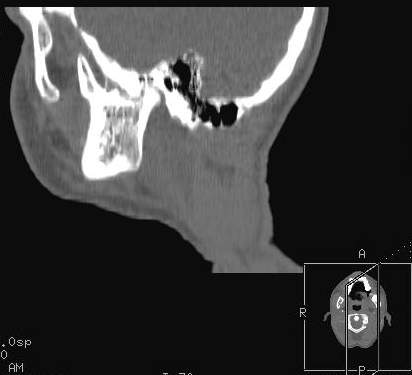

Пациент В., 13 лет. Диагноз: Костный анкилоз левого височно-нижнечелюстного сустава (ВНЧС), левосторонняя микрогения. Болеет с 2-х летнего возраста. Возможная причина развития анкилоза – воспалительный процесс (в первые 1,5 года жизни часто болел простудными заболеваниями, травму родители отрицают). В 3 и 5 лет проводилась редрессация – безуспешно. Прилагаются: ортопантомограмма, кадры СКТ с 3Д реконструкцией. Вопросы: определение тактики лечения – вид и сроки реконструктивно-пластической операции (этапов операции), а именно – неоартропластики и устранения микрогении, медикаментозная терапия в до- и послеоперационный период, ортодонтическое лечение.